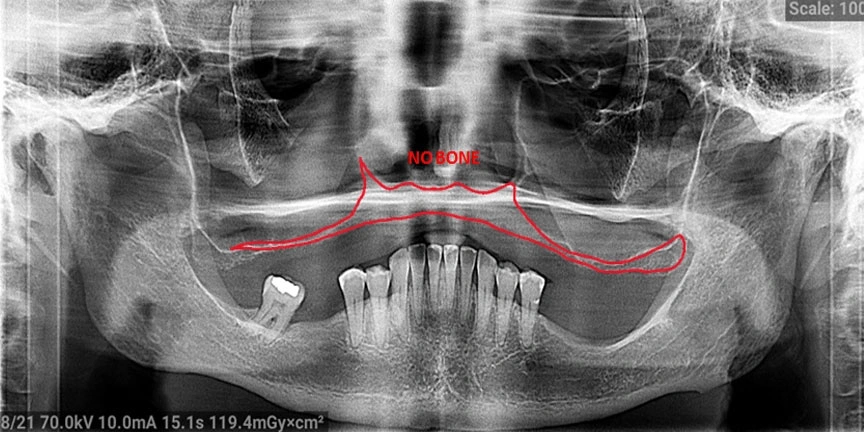

- Difficult Cases: We treat patients when other providers cannot manage.

Severe Bone Loss